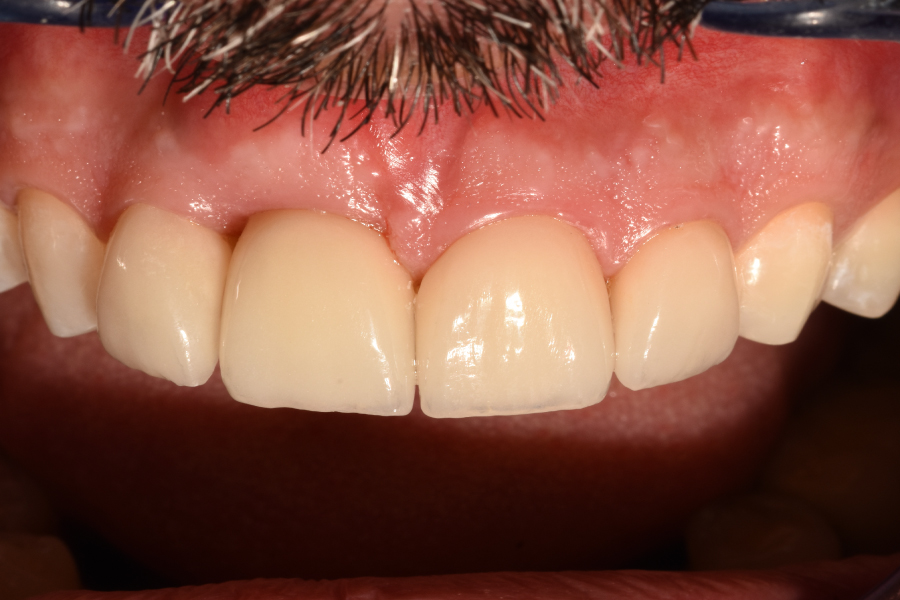

Figura 40

Figura 41

Figura 42

Figura 43

Figura 44

Figura 45

Figura 46

Figura 47

Figura 48

Figura 49